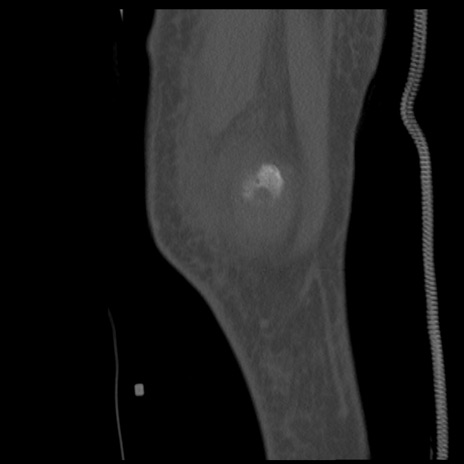

症例28 右膝関節CT(矢状断像)

右膝関節CT

横断像